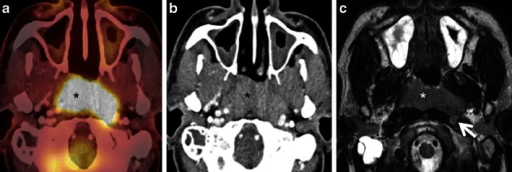

Diagnosis[edit | edit source]

Staging of nasopharyngeal carcinoma is based on clinical and radiologic examination. Most patients present with Stage III or IV disease.